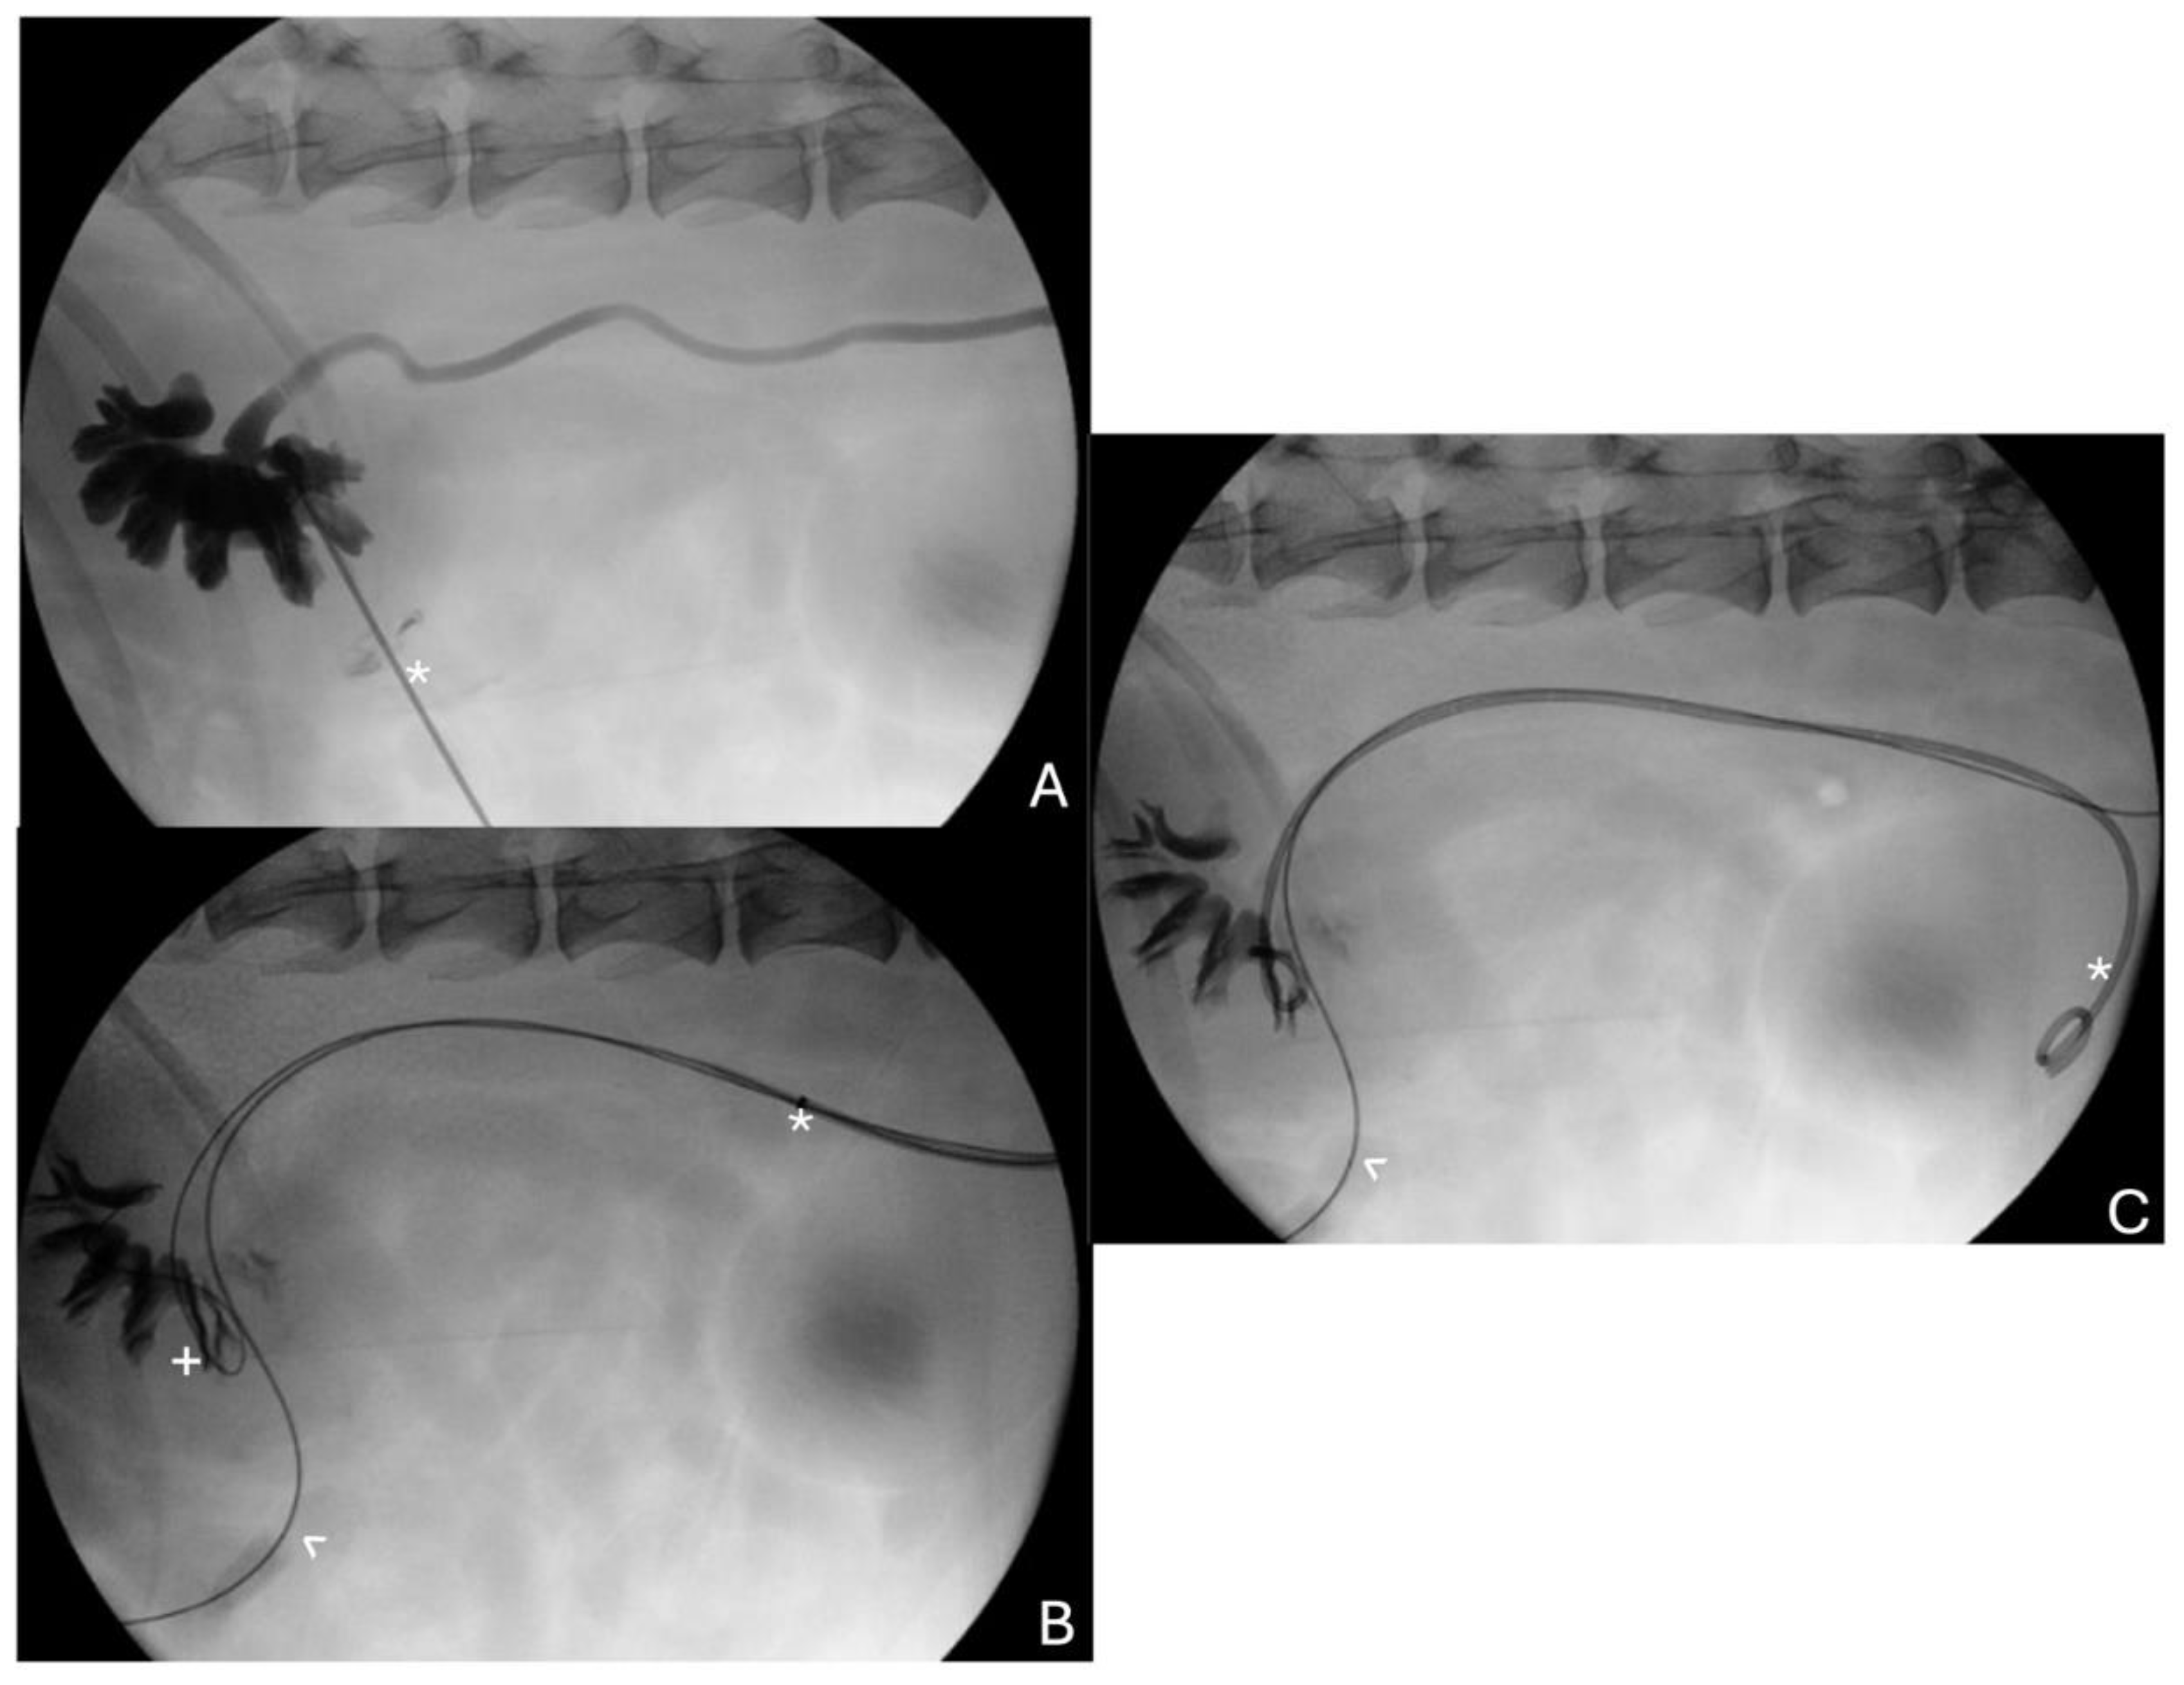

4.3. Palliative Stenting for Urethral and Ureteral Obstruction

4.3.1. Urethral Stenting

4.3.2. Ureteral Stenting

- Weisse, C.; Berent, A.; Todd, K.; Clifford, C.; Solomon, J. Evaluation of Palliative Stenting for Management of Malignant Urethral Obstructions in Dogs. J. Am. Vet. Med. Assoc. 2006, 229, 226–234. [Google Scholar] [CrossRef] [PubMed]

- Blackburn, A.L.; Berent, A.C.; Weisse, C.W.; Brown, D.C. Evaluation of Outcome Following Urethral Stent Placement for the Treatment of Obstructive Carcinoma of the Urethra in Dogs: 42 Cases (2004–2008). J. Am. Vet. Med. Assoc. 2013, 242, 59–68. [Google Scholar] [CrossRef]

- Berent, A.C.; Weisse, C.; Beal, M.W.; Brown, D.C.; Todd, K.; Bagley, D. Use of Indwelling, Double-Pigtail Stents for Treatment of Malignant Ureteral Obstruction in Dogs: 12 Cases (2006–2009). J. Am. Vet. Med. Assoc. 2011, 238, 1017–1025. [Google Scholar] [CrossRef]